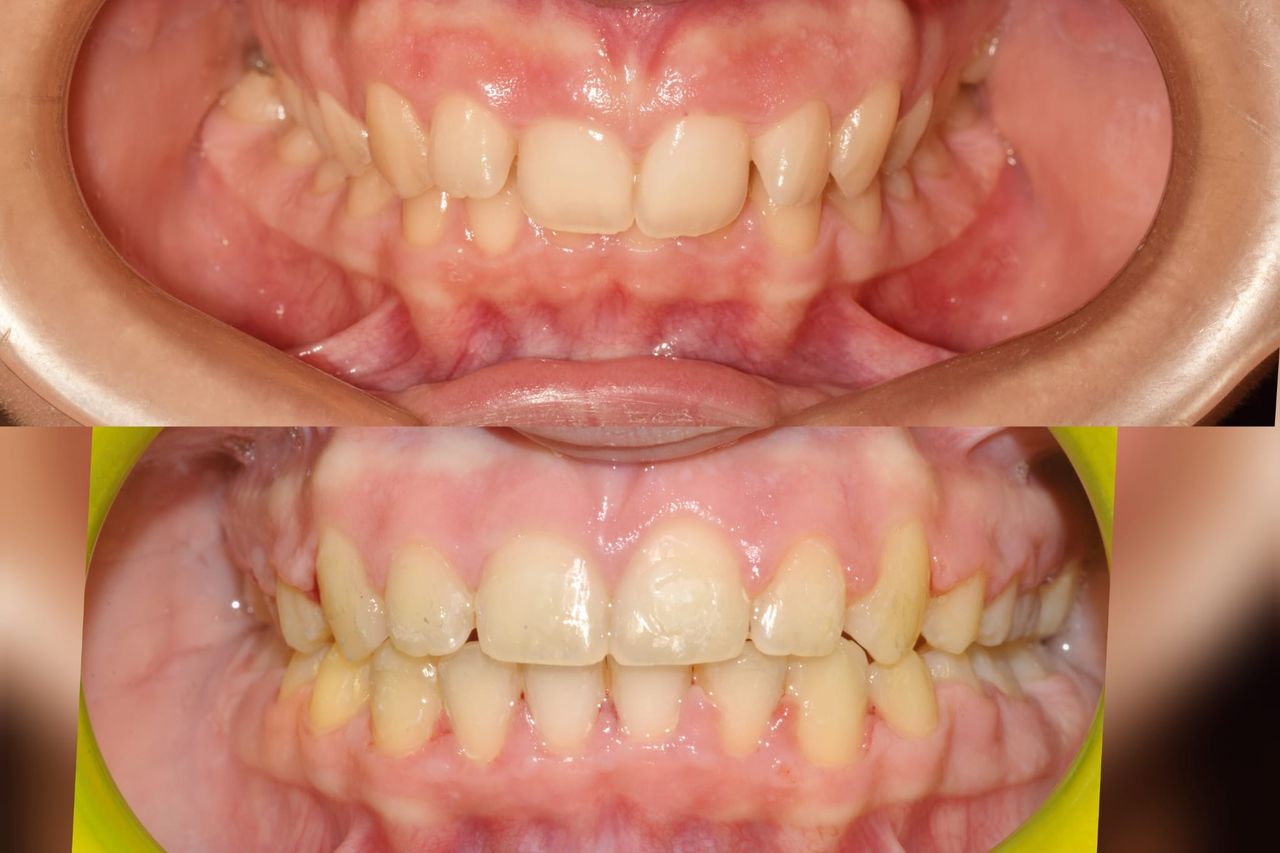

Il dottor Gianluca del Vecchio si occupa esclusivamente di ortognatodonzia, grazie anche alla collaborazione multidisciplinare di una équipe davvero entusiasmante e all’utilizzo di strumenti diagnostici e terapeutici all’avanguardia in ortognatodonzia. Particolare è la sua capacità di condurre i giovani pazienti ad affrontare, nella massima sicurezza emotiva e clinica, qualsiasi eventuale condizione di dolore derivante, ad esempio, da carie o da altre patologie, ma soprattutto di risolvere tutte quelle condizioni di “denti storti”, così spesso causa di disagio psicologico o di fenomeni deprecabili, quale il bullismo.

L’ortognatodonzia è la disciplina che si occupa dell’ortopedia delle ossa mascellari, interviene sulla crescita delle stesse modificando la posizione dei denti secondo quanto necessario. Così la pedodonzia, la seconda disciplina che si occupa, ma in modo esclusivo, dei bambini, affronta tutte le classiche patologie del cavo orale, quando i pazienti sono in età scolare.

Queste le ragioni che consentono di trattare le malocclusioni, sia dei bambini che degli adulti, con protocolli scientificamente validati come i più veloci, affidabili e confortevoli.

Foto e video